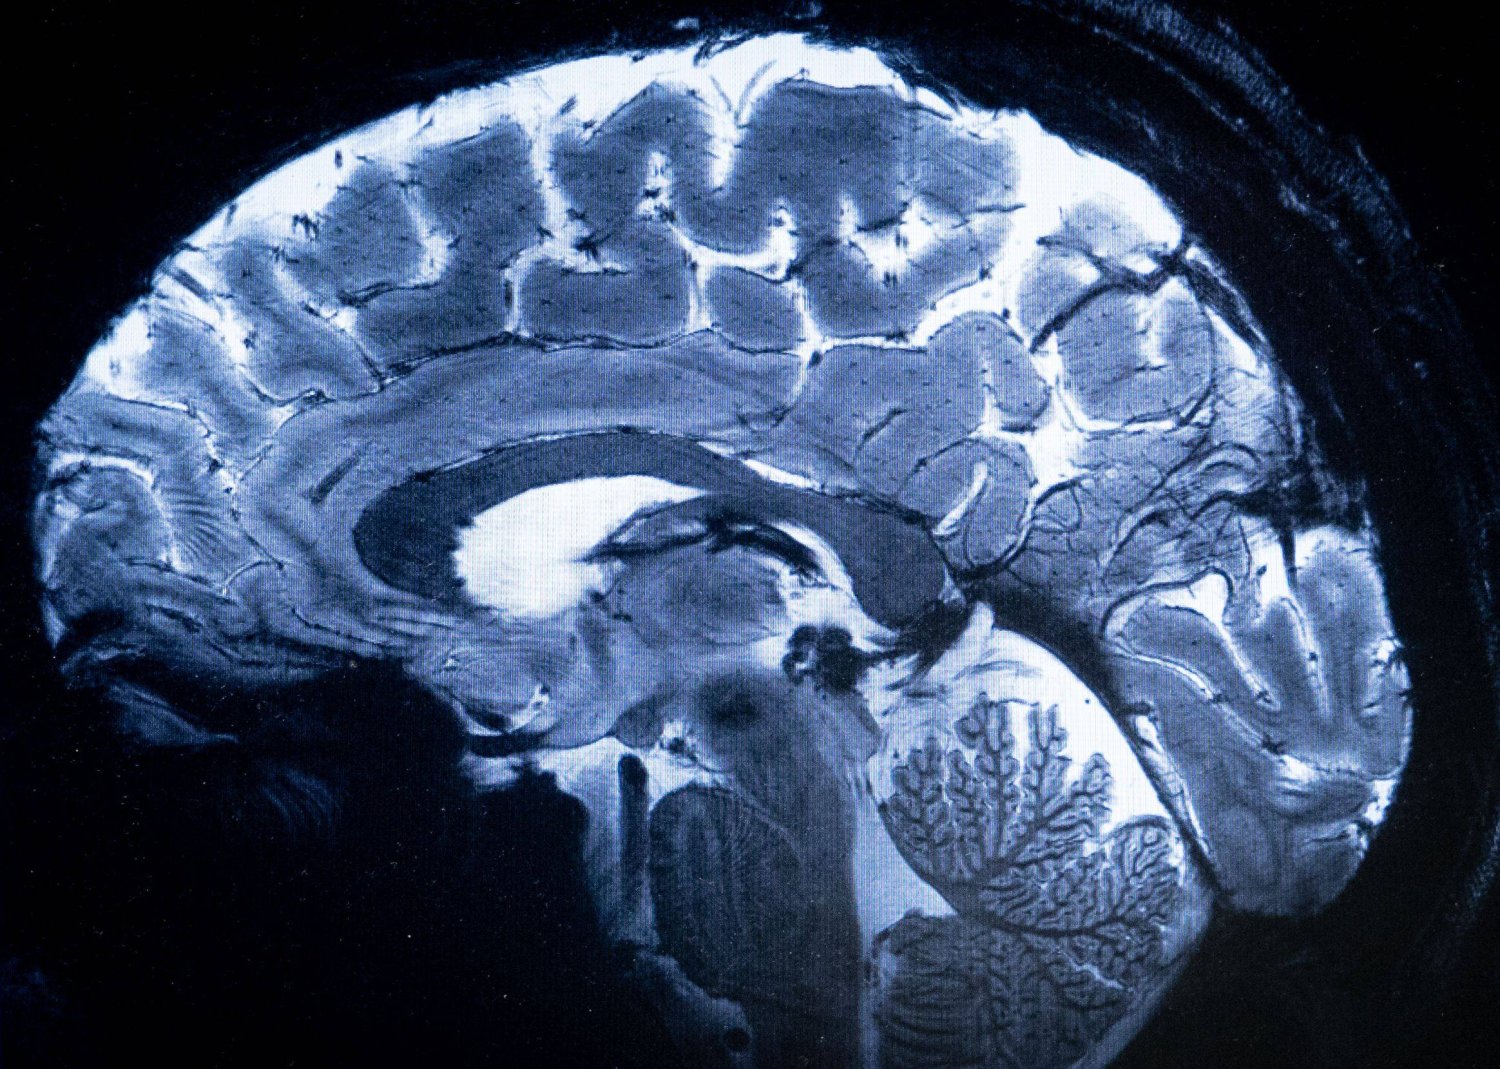

وفي التجربة التي أجرتها الدراسة المنشورة في مجلة "نيتشر ميتابوليزم"، وشملت 75 مشاركا، خضع المشاركون لفحوصات بالرنين المغناطيسي بعد شرب 3 أنواع من السوائل: الماء، محلول يحتوي على السكرالوز، وآخر محلى بالسكر.

وأظهرت النتائج أن "السكرالوز" زاد من النشاط في منطقة تحت المهاد، المسؤولة عن التحكم في الجوع، وعزز الاتصال بين مناطق الدماغ المرتبطة بالتحفيز واتخاذ القرار.